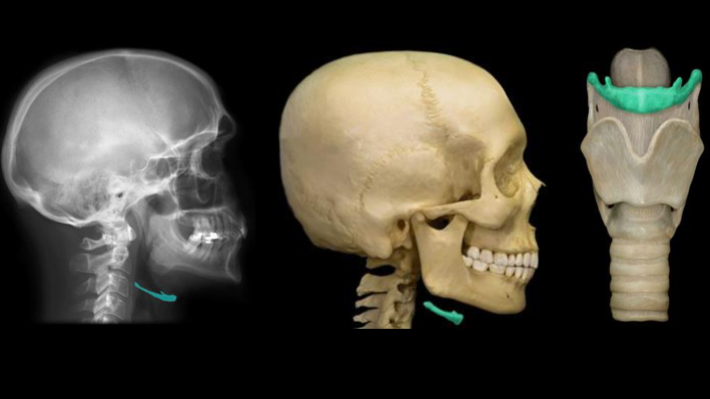

What is the “floating bone under the jaw” that is highlighted in this image called?

hyoid